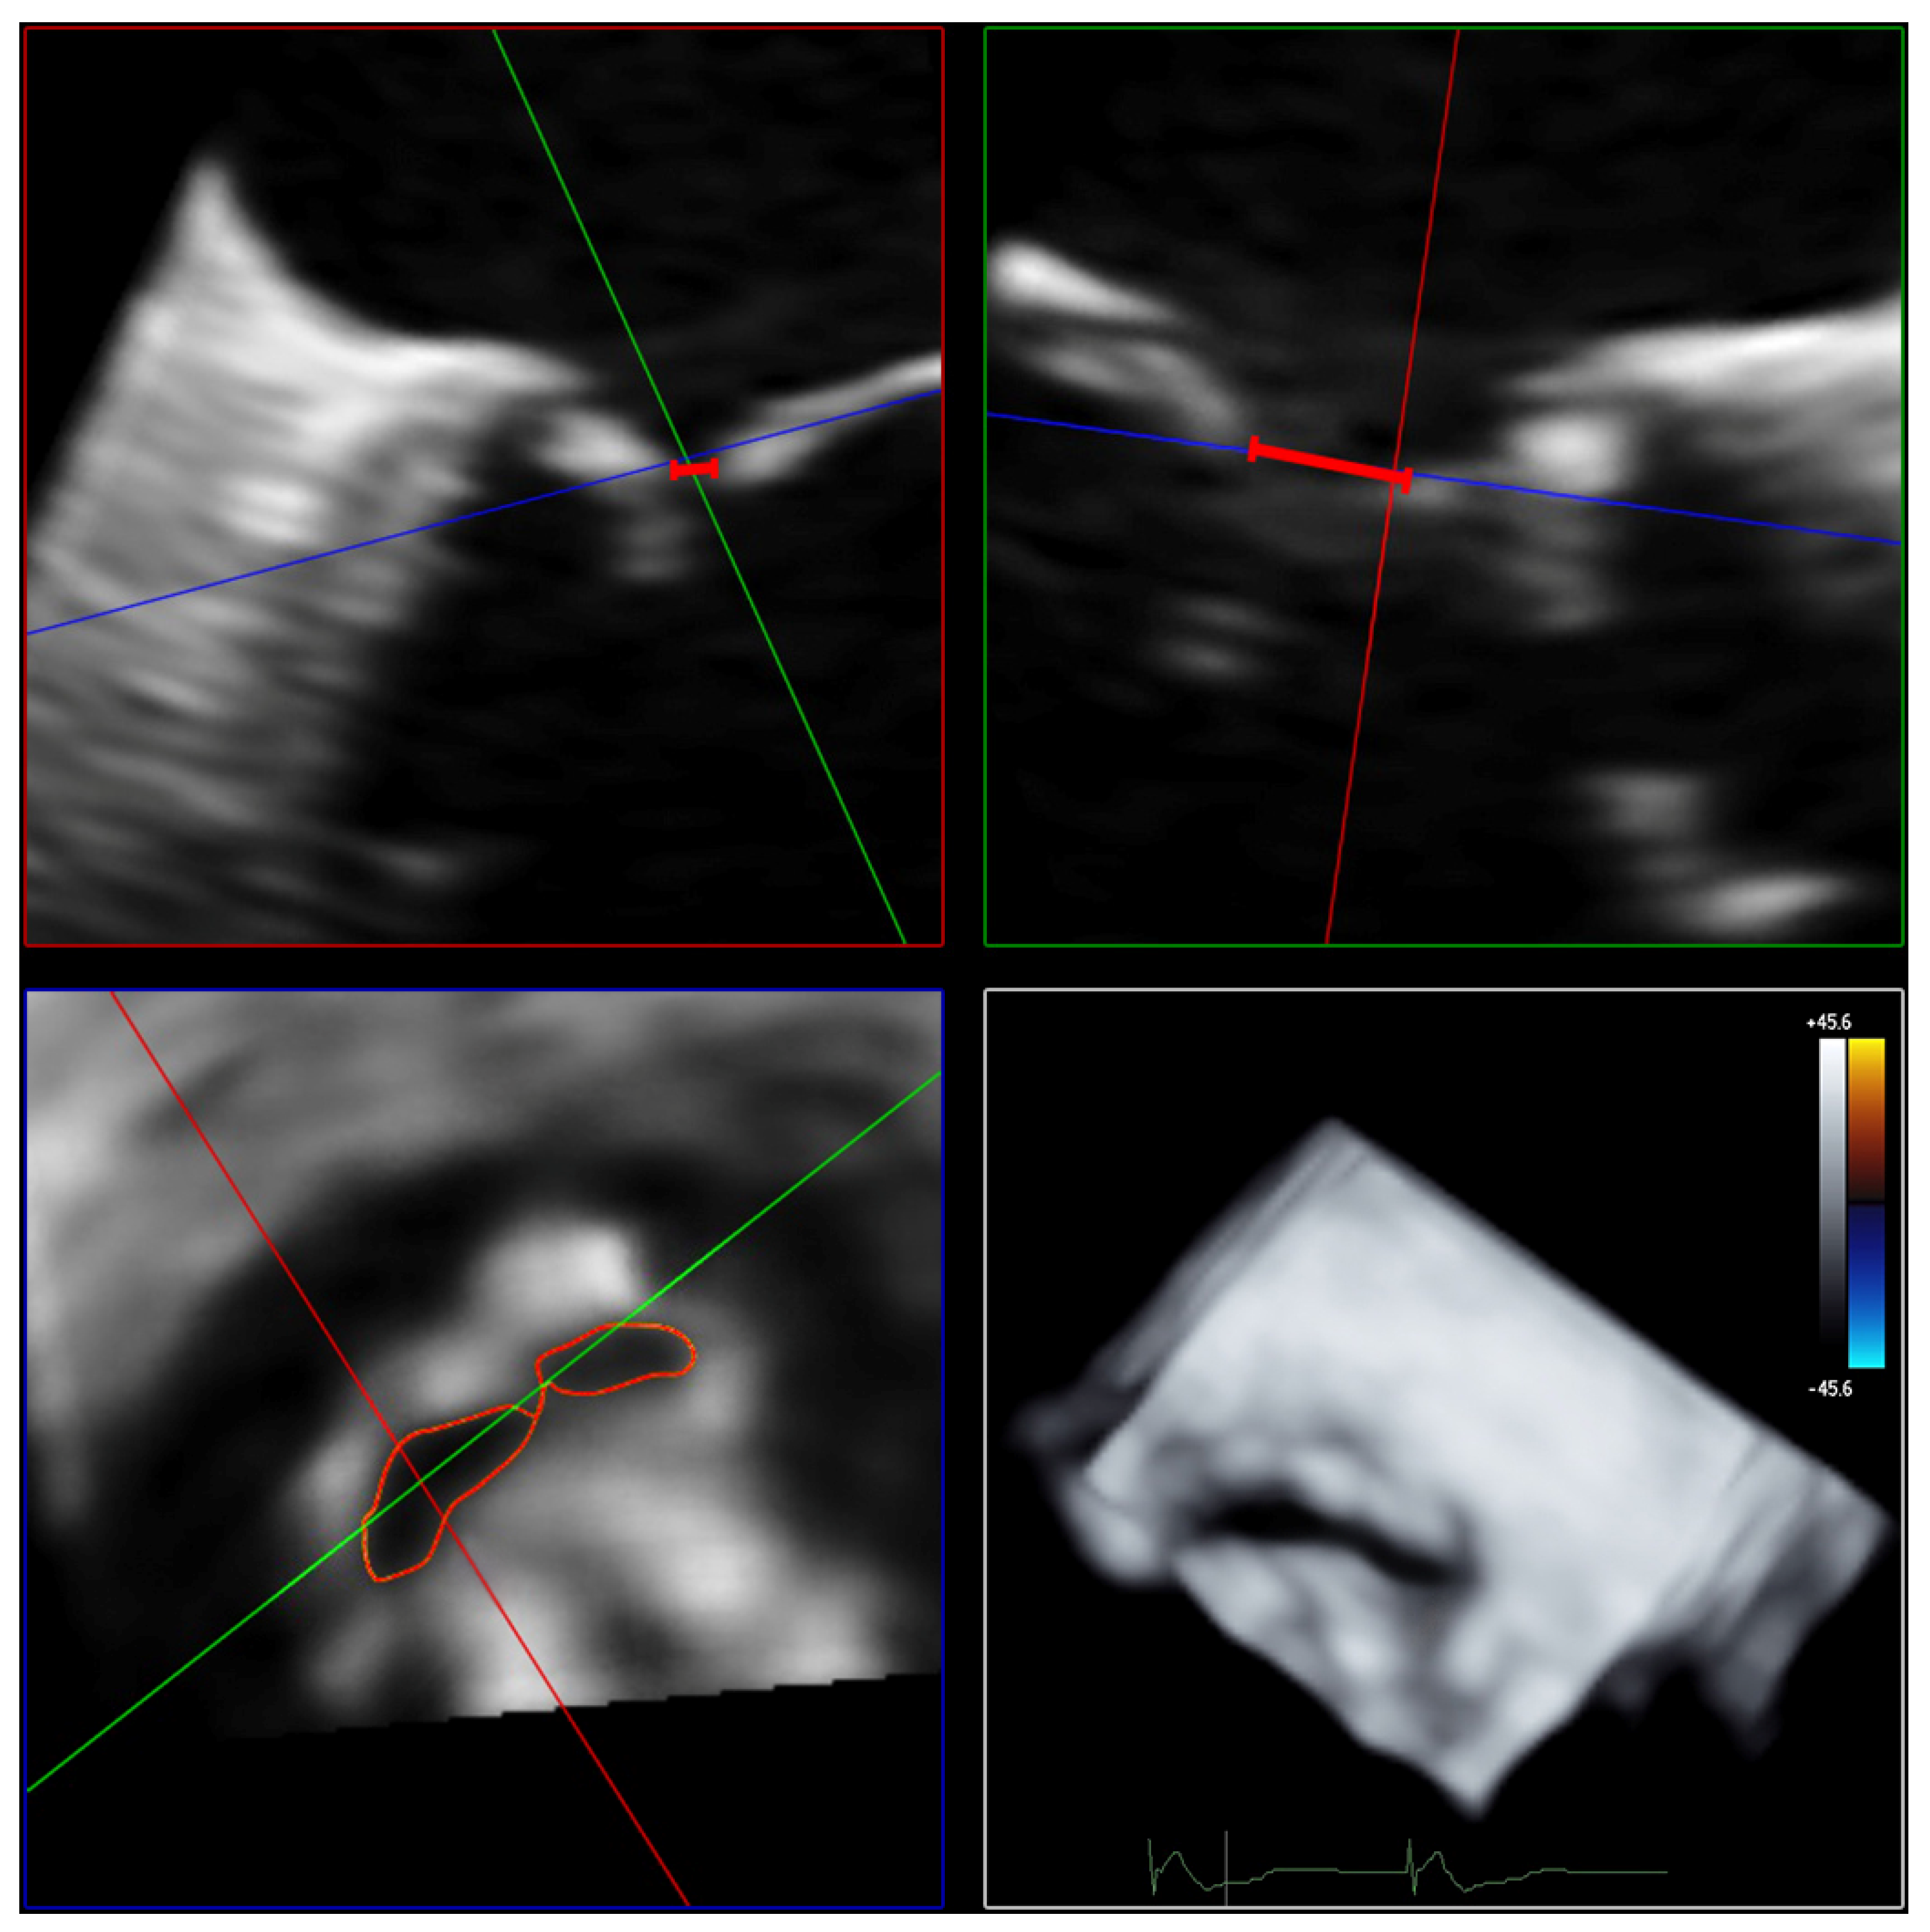

The AROA was measured by subtracting the color from the full-volume 3D color Doppler datasets. The AROA was planimetrically adjusted to the minimum cross-sectional plane of the anatomic regurgitation defect between the mitral valve leaflets (Figure 4). The area of the minimal anatomic regurgitation defect was measured by tracing the boundary of the leaflets. Analogous to the measurement of the 3D VCA, settings for brightness and contrast were fixed at 50% values and smoothening.

Figure 4. Determination of AROA using multiplanar reconstruction of the 3D color Doppler dataset without color. Echocardiographic images with 3 slice planes and 3D reconstruction (lower right) of the 3D color Doppler dataset (mid-systolic) with subtraction of color. Planimetric fitting of the 2 upper planes along the course of the color Doppler jet; third plane (lower left) adjustment orthogonal to planes along the jet. Then, subtraction of color and finding the minimum coaptation defect between the mitral valve leaflets using translation and tilting of the third plane; manual measurement of the minimum coaptation defect using outlining. Abbreviations: AROA = anatomical regurgitation orifice area; 3D = three-dimensional.